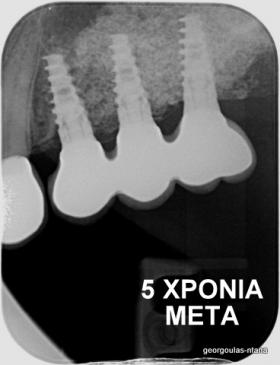

Στην ασθενή αυτή πραγματοποιήθηκε ανοικτή ανύψωση ιγμορείου άνω αριστερά. Σε πρώτη φάση πραγματοποιήθηκε η οστική αύξηση και 6 μήνες μετά τοποθετήθηκαν 3 εμφυτεύματα. Τόσο στην πανοραμική όσο και στην τομογραφία κωνικής δέσμης (CBCT) που πραγματοποιήθηκαν 6 μήνες μετά την ανύψωση είναι εμφανής ο σχηματισμός οστού. Η τελευταία ακτινογραφία και φωτογραφία λήφθηκαν 5 χρόνια μετά την προσθετική αποκατάσταση.